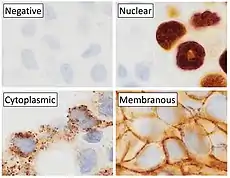

Diagnostic IHC markers

IHC is an excellent detection technique and has the tremendous advantage of being able to show exactly where a given protein is located within the tissue examined. It is also an effective way to examine the tissues. This has made it a widely used technique in neuroscience, enabling researchers to examine protein expression within specific brain structures. Its major disadvantage is that, unlike immunoblotting techniques where staining is checked against a molecular weight ladder, it is impossible to show in IHC that the staining corresponds with the protein of interest. For this reason, primary antibodies must be well-validated in a Western Blot or similar procedure. The technique is even more widely used in diagnostic surgical pathology for immunophenotyping tumors (e.g. immunostaining for e-cadherin to differentiate between DCIS (ductal carcinoma in situ: stains positive) and LCIS (lobular carcinoma in situ: does not stain positive)[11]). More recently, immunohistochemical techniques have been useful in differential diagnoses of multiple forms of salivary gland, head, and neck carcinomas.[12]

A variety of molecular pathways are altered in cancer and some of the alterations can be targeted in cancer therapy. Immunohistochemistry can be used to assess which tumors are likely to respond to therapy, by detecting the presence or elevated levels of the molecular target.

Many proteins shown to be highly upregulated in pathological states by immunohistochemistry are potential targets for therapies utilising monoclonal antibodies. Monoclonal antibodies, due to their size, are utilized against cell surface targets. Among the overexpressed targets are members of the EGFR family, transmembrane proteins with an extracellular receptor domain regulating an intracellular tyrosine kinase.[17] Of these, HER2/neu (also known as Erb-B2) was the first to be developed. The molecule is highly expressed in a variety of cancer cell types, most notably breast cancer. As such, antibodies against HER2/neu have been FDA approved for clinical treatment of cancer under the drug name Herceptin. There are commercially available immunohistochemical tests, Dako HercepTest, Leica Biosystems Oracle[18] and Ventana Pathway.[19]

Similarly, EGFR (HER-1) is overexpressed in a variety of cancers including head and neck and colon. Immunohistochemistry is used to determine patients who may benefit from therapeutic antibodies such as Erbitux (cetuximab).[20] Commercial systems to detect EGFR by immunohistochemistry include the Dako pharmDx.